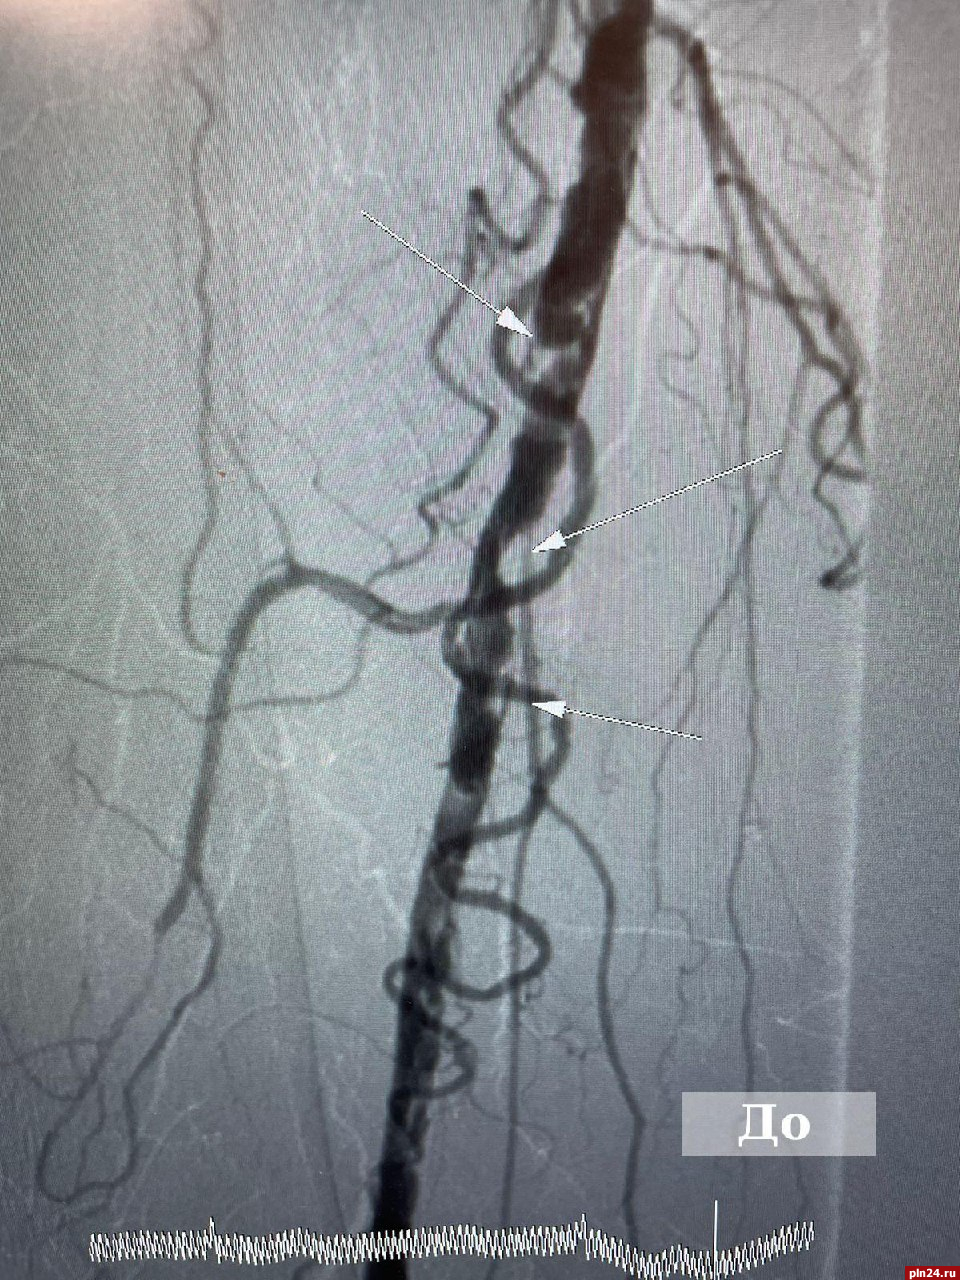

На фото до хирургического вмешательства видно выраженное поражение артерии правой нижней конечности. После имплантации стента восстановлена проходимость артерии.